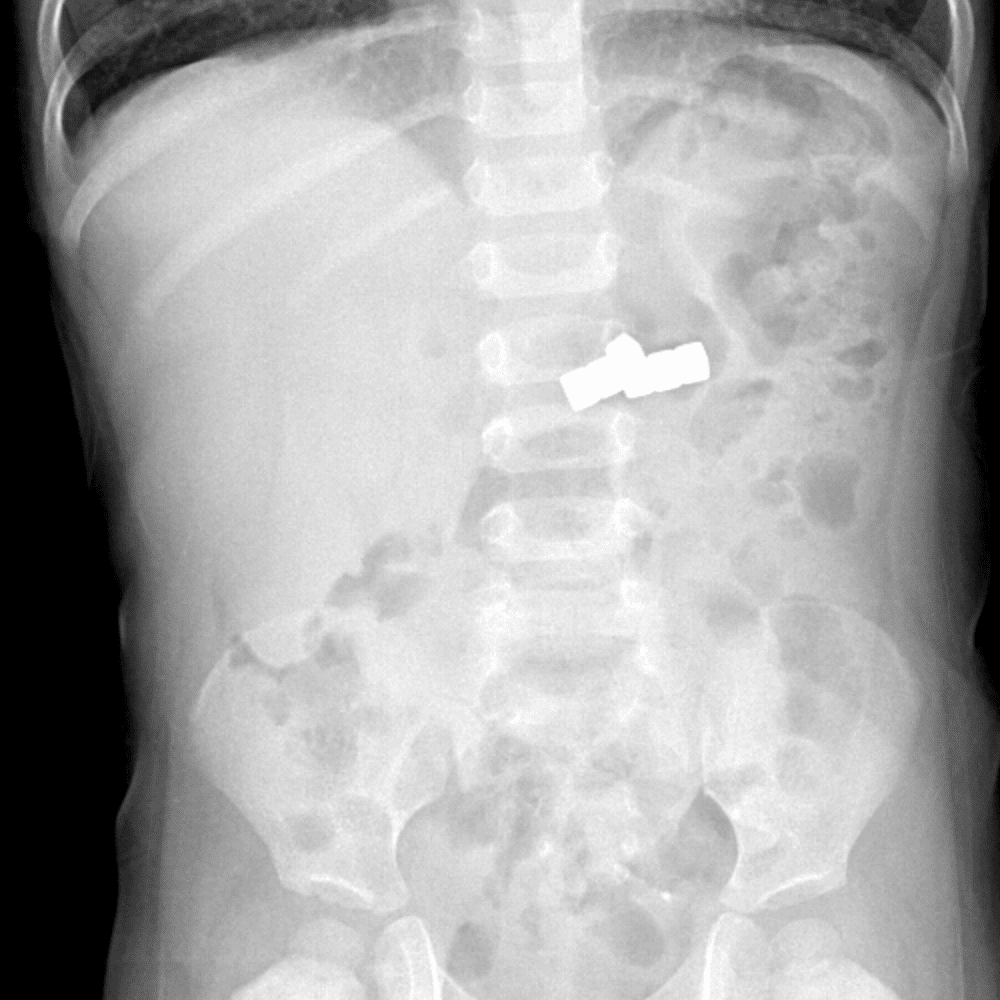

Peds Abdomen

Practice

Simulates call by including subtle or difficult cases and some normals.

30 cases